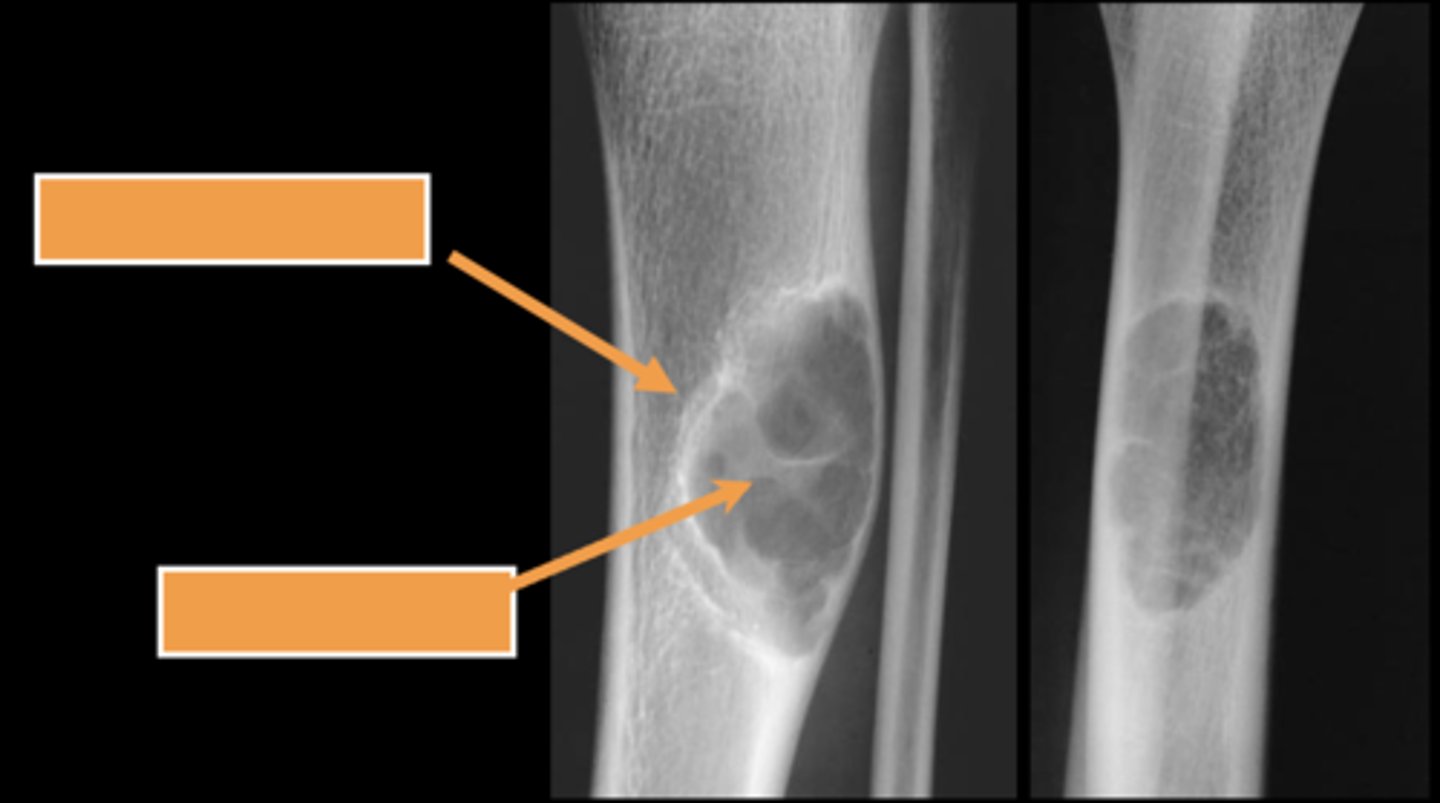

58

New cards

Geographic bone blister

ID radiographic feature of non-ossifying fibroma indicated by top arrow

<p>ID radiographic feature of non-ossifying fibroma indicated by top arrow</p>

59

Septations

ID radiographic feature of non-ossifying fibroma indicated by bottom arrow

<p>ID radiographic feature of non-ossifying fibroma indicated by bottom arrow</p>